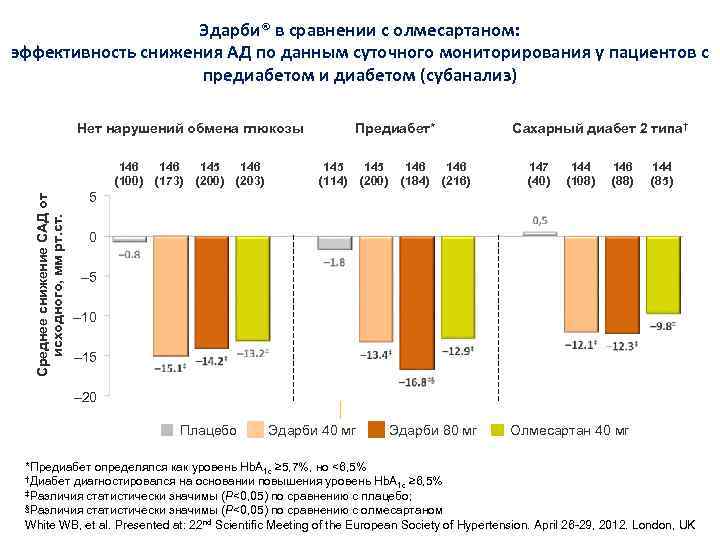

Эдарби® в сравнении с олмесартаном: эффективность снижения АД по данным суточного мониторирования у пациентов с предиабетом и диабетом (субанализ) Нет нарушений обмена глюкозы Среднее снижение САД от исходного, мм рт. ст. 146 (100) 146 (173) 145 (200) 146 (203) Предиабет* 145 (114) 145 (200) 146 (184) Сахарный диабет 2 типа† 146 (216) 147 (40) 144 (108) 146 (88) 144 (85) 5 0 – 5 – 10 – 15 – 20 Плацебо Эдарби 40 мг Эдарби 80 мг Олмесартан 40 мг *Предиабет определялся как уровень Hb. A 1 c ≥ 5, 7%, но <6, 5% †Диабет диагностировался на основании повышения уровень Hb. A ≥ 6, 5% 1 c ‡Различия статистически значимы (P<0, 05) по сравнению с плацебо; §Различия статистически значимы (P<0, 05) по сравнению с олмесартаном White WB, et al. Presented at: 22 nd Scientific Meeting of the European Society of Hypertension. April 26 -29, 2012. London, UK

Эдарби® в сравнении с олмесартаном: эффективность снижения АД по данным суточного мониторирования у пациентов с предиабетом и диабетом (субанализ) Нет нарушений обмена глюкозы Среднее снижение САД от исходного, мм рт. ст. 146 (100) 146 (173) 145 (200) 146 (203) Предиабет* 145 (114) 145 (200) 146 (184) Сахарный диабет 2 типа† 146 (216) 147 (40) 144 (108) 146 (88) 144 (85) 5 0 – 5 – 10 – 15 – 20 Плацебо Эдарби 40 мг Эдарби 80 мг Олмесартан 40 мг *Предиабет определялся как уровень Hb. A 1 c ≥ 5, 7%, но <6, 5% †Диабет диагностировался на основании повышения уровень Hb. A ≥ 6, 5% 1 c ‡Различия статистически значимы (P<0, 05) по сравнению с плацебо; §Различия статистически значимы (P<0, 05) по сравнению с олмесартаном White WB, et al. Presented at: 22 nd Scientific Meeting of the European Society of Hypertension. April 26 -29, 2012. London, UK